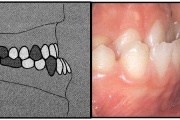

Vali sind huvitav pilt ja me näitame sellega seotud haigust ja sümptomeid